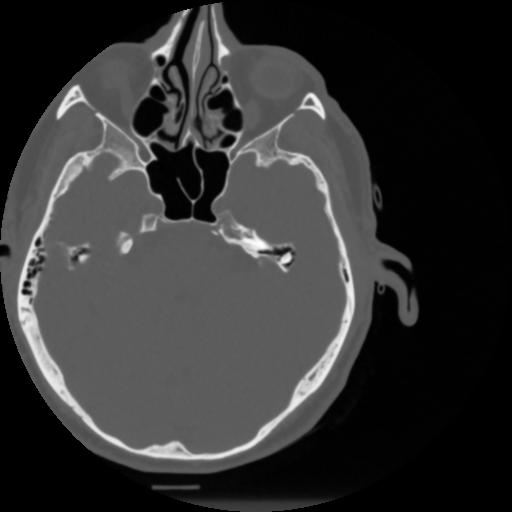

4 CEREBRO,,Vol,0.5,CEREBRO,,